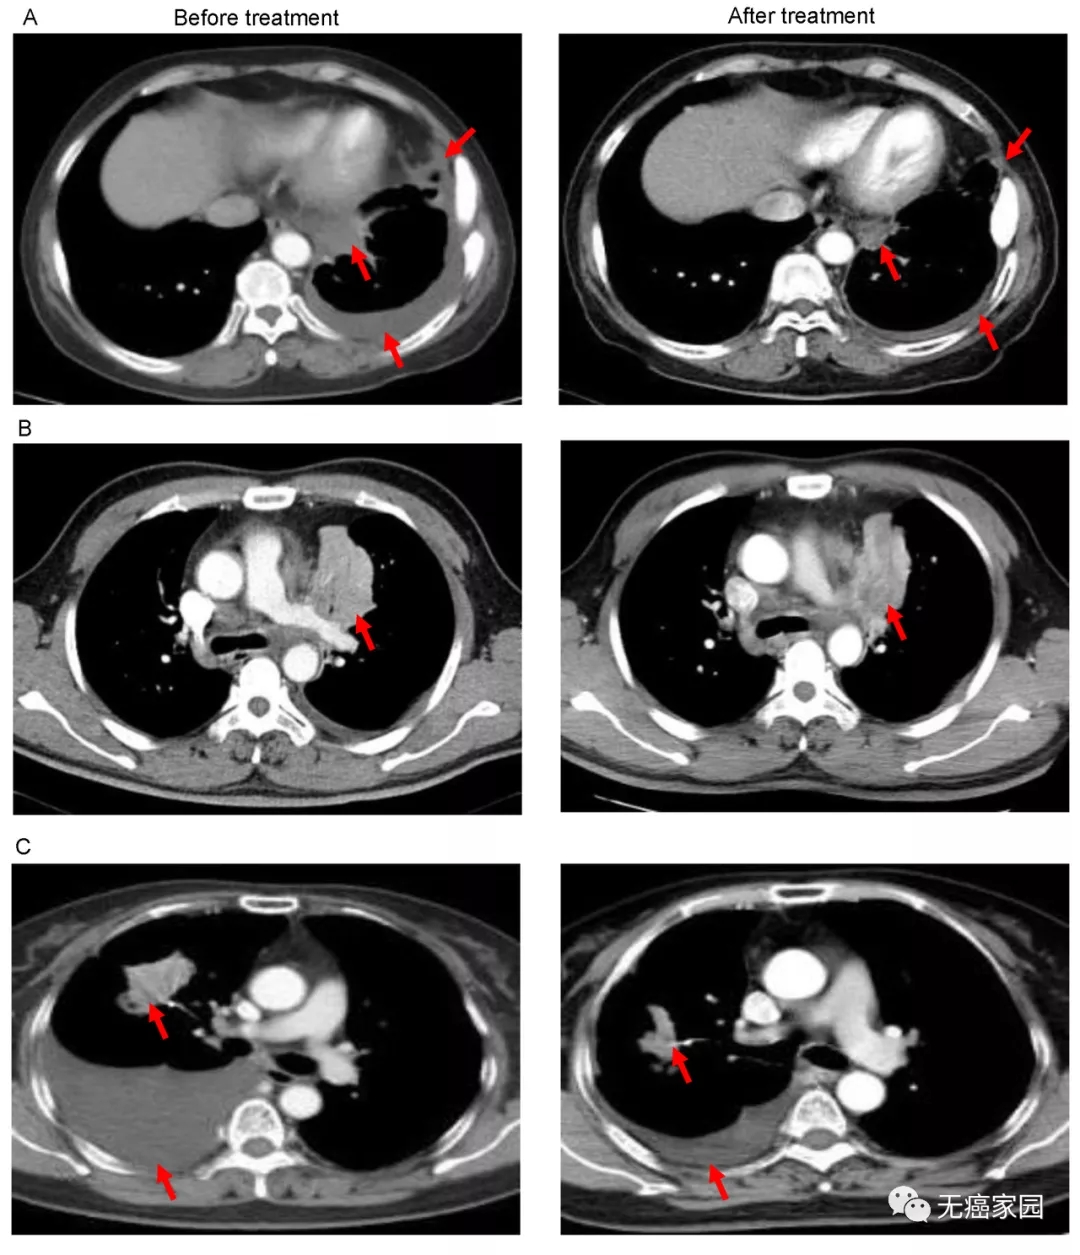

301医院在国内率先开展CAR-T疗法,成果显著。韩为东教授曾报道过利用EGFR为靶点的CAR-T治疗EGFR表达强阳性(EGFR表达超过50%)的晚期难治性的非小细胞肺癌患者。

研究结果显示,其中11例患者疗效可评价:2例患者肿瘤明显缩小,5例疾病稳定。

图A中患者1在输注CAR-T细胞后,通过CT扫描显示其胸腔积液减少,转移性肺门淋巴结和胸膜结节轻度缩小(箭头)。

图B中CT图像显示患者8的原发性肿瘤缩小(箭头);

图C中CT检查发现CAR-T治疗后患者9的胸腔积液吸收和肺部病变明显消退。